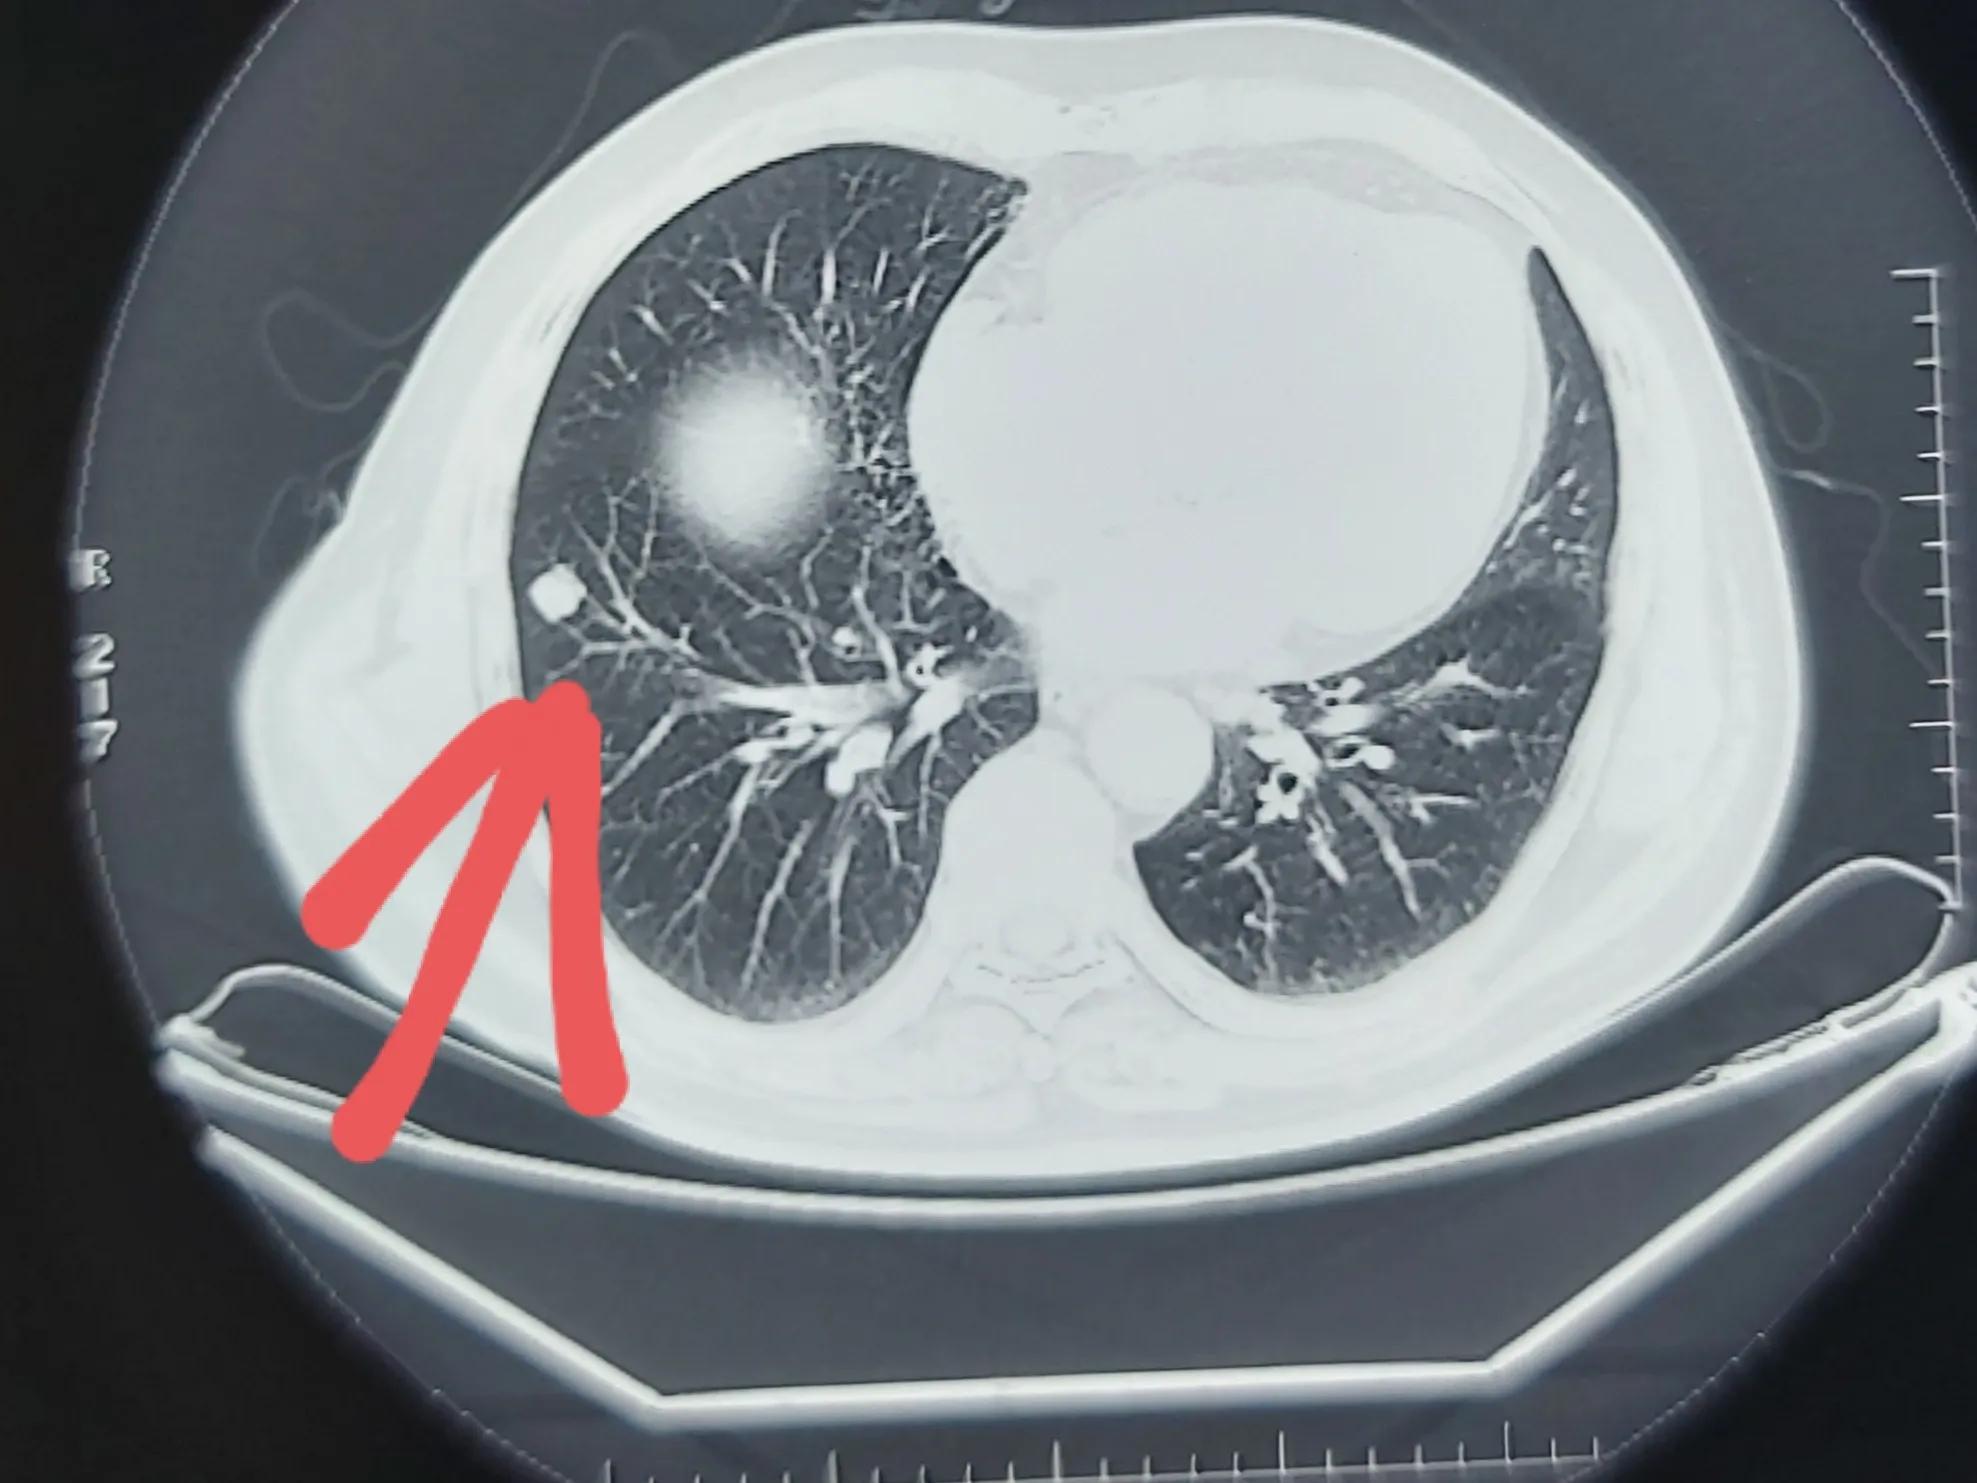

他在网上看到了我曾经写过肺癌七种自身抗体的患教短文,于是联系到我,把资料发过来听听我的意见。我确实写过几个关于肺癌自身抗体的病例,最近的一篇是自身抗体阴性,但切出来是肺癌。那有没有可能性是反过来的,比如说自身抗体阳性,但切出来不是肺癌呢?这种情况临床中也不罕见,我下面举的这个例子就是,这位患者右肺有一个结节,看了几个医生,有的认为肺癌可能性比较大,甚至报告也说考虑肿瘤性病变,他的肺癌自身抗体就是阳性。但我看这片子,给我的感觉这是一个良性的错构瘤,不是肺癌。手术切下来的结果也印证了我的推断,确实不是肺癌。